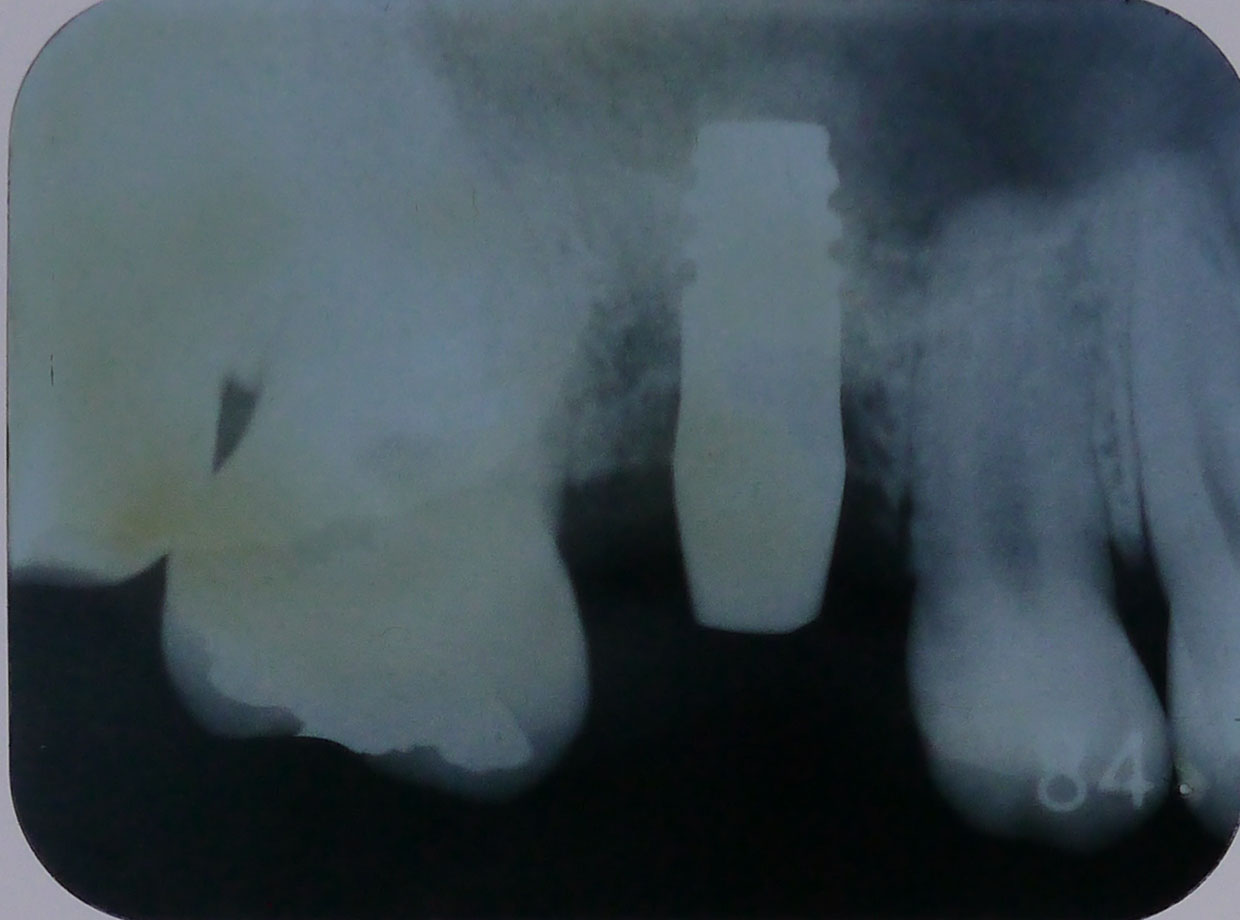

レントゲン画像2

平成24年8月17日、4ヶ月半後のレントゲン画像 だいぶ骨が出来ている

CT画像3

平成29年12月6日、5年経過後の定期検診時のレントゲン画像

右上6番、インプラントの先端近くまで骨があり、十分機能している